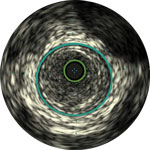

Behandlungsplan Beispiel 1

Lumen

Exzentrische fibröse Plaque mit tiefliegendem Calcium

Schallschatten

Gefässgrösse: 5,5 mm Durchmesser Plaquemorphologie: fibröse Plaque mit intimalem und mittlerem Calcium Plaquegeometrie: exzentrische Läsion Position des Führungsdrahtes: wahres Lumen

Quick-Cross-Katheter: souverän komplexe Morphologien durchqueren Direktionale Atherektomie mit Phoenix: frontal zum Schneiden, Erfassen und Freilegen gemischter Morphologien, einschliesslich Kalzium; Möglichkeit der Richtungssteuerung für grösseren Lumengewinn AngioSculpt Scoring-Ballonkatheter: Calcium messen, um eine Dissektion zu reduzieren4 Stellarex DCB: entwickelt für hohe Leistungsfähigkeit bei Kalzifizierungen